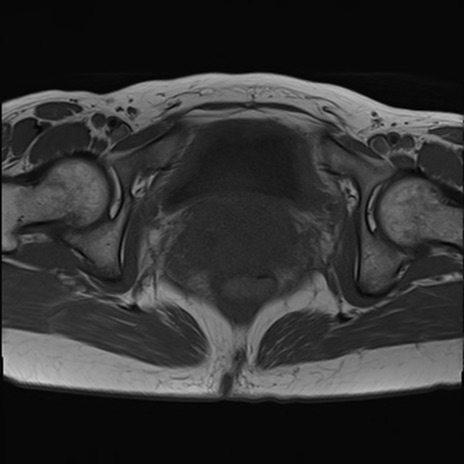

症例39 T1WI(横断像)

MRI(4日後)